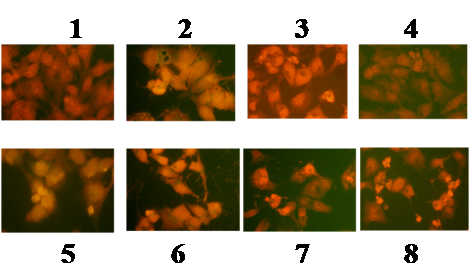

Fluorescence imaging

Effect of kaempferol-doxorubicin/cisplatin combination on apoptotic cell death of cancer cells

On the basis of strong growth inhibition by the synergistic effect of kaempferol-doxorubicin or cisplatin combination on HCT-15 and MDA MB 231 cells, the investigation was carried to show their effect on apoptotic morphological changes. To evaluate the effect of kaempferol and doxorubicin or cisplatin, treated cells were stained with propidium iodide. The results were compared with untreated control cells. The stained cells showed fragmentation and condensation of chromatin and other morphological features characteristic of apoptotic cells in both the cancer cells, whereas untreated control cells were not identified with nuclear alterations and showed a normal nuclear morphology characterised by diffused chromatin structure. The combinational dose concentrations of kaempferol, doxorubicin or cisplatin and treatment design, were the same as that of other studies for both cell lines. As shown in (fig. 7, 8), the apoptotic cell population was increased in both HCT-15 and MDA MB 231 cell lines when treated with doxorubicin or cisplatin in combination with kaempferol.

Apoptotic death of cancer cells is considered to be a potential anti-cancer mechanism, which could control their proliferation [1, 10]. Recently, the regulation of apoptosis has been proposed as a promising target for cancer chemotherapy [19, 20]. Consistent with these reports, the data of our present study show clearly that kaempferol and doxorubicin/cisplatin combination induces strong apoptotic cell death that was ~ 3 fold higher than each agent alone.

Fig. 8: Morphologial alterations of MDA MB 231 cells treated with kaempferol in combination with chemotherapeutic drugs, cells treated with concentrations. (1) control; (2) kaempferol (64 µg/ml); (3)-doxorubicin (44 µg/ml); (4)-cisplatin (40 µg/ml); (5)-kaemferol (64 µg/ml)+doxorubicin (44 µg/ml); (6)-kaemferol (32 µg/ml) doxorubicin (18 µg/ml); (7)-kaemferol (64 µg/ml)+cisplatin (40 µg/ml); (8)-kaemferol(32 µg/ml)+cisplatin (15 µg/ml). Cells were visualized under fluorescence microscope (Magnification X200)